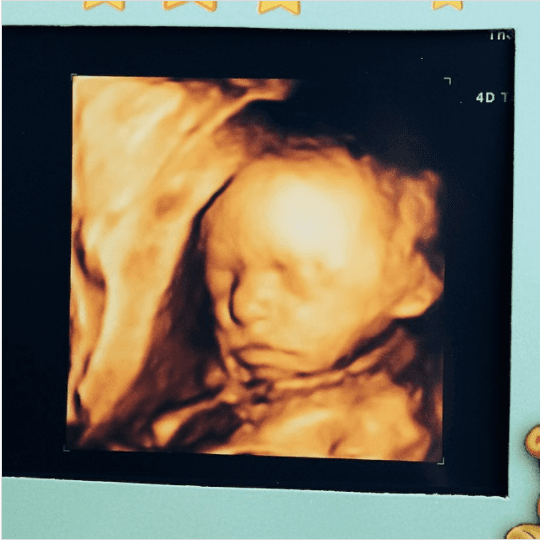

Ahora es toda una princesa, pero parece que fue ayer que Jacky Bracamontes anunciaba que Caro venía en camino. En abril del 2014, Jacky expuso con gran felicidad su segundo embarazo. Con el breve mensaje de “Hola a todos!!! Soy #Carolina”, dio a conocer la llegada de su segunda hija al lado de Martín Fuentes. Desde entonces se supo que Caro nacería los primeros días de julio. Y así fue, el 9 de julio del 2014 nació la princesa de papá.